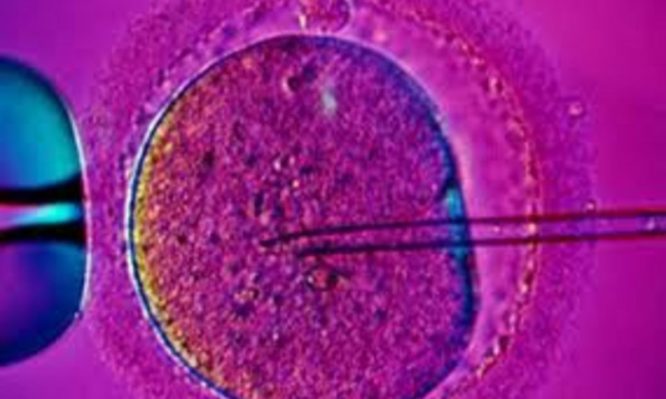

Καιρό τώρα νεαρά ζευγάρια που επιχειρούν να κάνουν παιδί βασανίζονται σε ουρές προκειμένου να πάρουν έγρκιση για φάρμακα εξωσωματικής αλλά και για πρόκληση ωοθυλακιορρηξίας καθώς και για χορήγηση γοναδοτροπινών σε άνδρες.

Τα μέλη των Επιτροπών γνωματεύουν επί αιτημάτων ασφαλισμένων για έγκριση προσπαθειών ιατρικώς υποβοηθούμενης αναπαραγωγής, πρόκλησης ωοθυλακιορρηξίας καθώς και χορήγησης γοναδοτροπινών σε άνδρες, σύμφωνα με τα οριζόμενα στον Ενιαίο Κανονισμό Παροχών (ΕΚΠΥ) του ΕΟΠΥΥ. Για πληροφορίες το τηλέφωνο επικοινωνίας είναι 210 8110684.

Και αυτό επειδή με τον νέο κανονισμό του ΕΟΠΥΥ, τα ζευγάρια οφείλουν να περνάνε τη διαδικασία της επιτροπής ακόμα και για την πολύ απλούστατη πρόκληση ωοθυλακιορυξίας.

Στο παρελθόν περνούσαν από επιτροπή μόνο στην περίπτωση εξωσωματικής γονιμοποίησης.